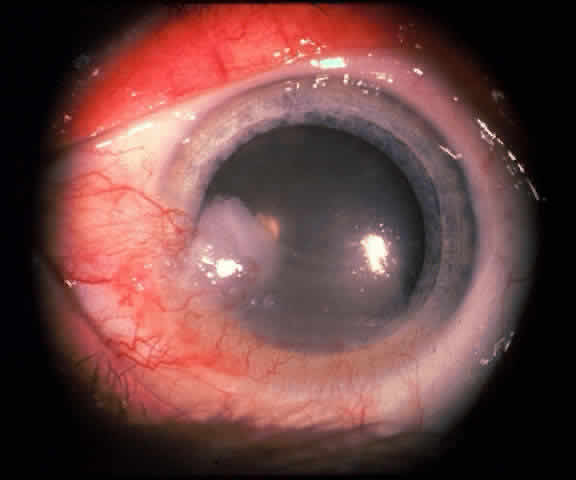

The epithelial dysplastic lesions—conjunctival intraepithelial neoplasia and squamous cell carcinoma—almost always begin at the limbus, most commonly in the interpalpebral zone.57,58 The initial appearance is a gelatinous, gray lesion with some thickening (Fig. 3). There may be increased vascularization. The epithelial changes may extend onto the cornea, causing a hazy, gray appearance. Tumor vascularity lags behind the lead margin of the epithelial change. As the lesions progress from dysplastic to carcinomatous, they become thicker, more vascularized and may show keratinization, giving a leukoplakic appearance (Fig. 4). Lesions confined to the epithelium move freely over the sclera, whereas invasive lesions are fixed to underlying tissue. Occasionally squamous cell carcinomas appear identical to classic papillomas.

Fig. 8. Conjunctival intraepithelial neoplasia. Gray, gelatinous mass is centered at limbus and has prominent vessels. A veil of intraepithelial disease extends laterally across the inferior third of the cornea.